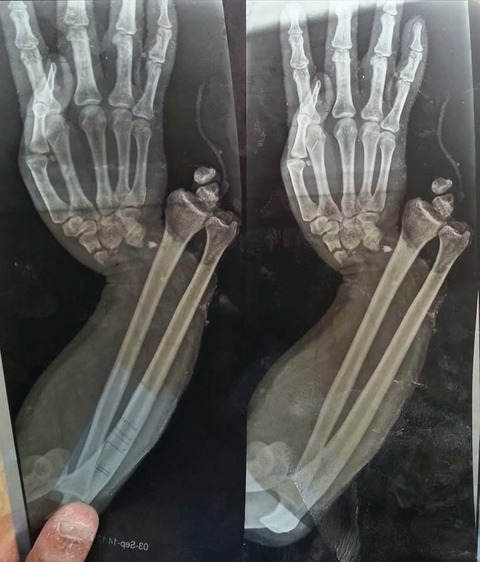

【画像あり】骨、逝くwwwwwwww

骨折

マジで痛そう…

複雑骨折じゃん…